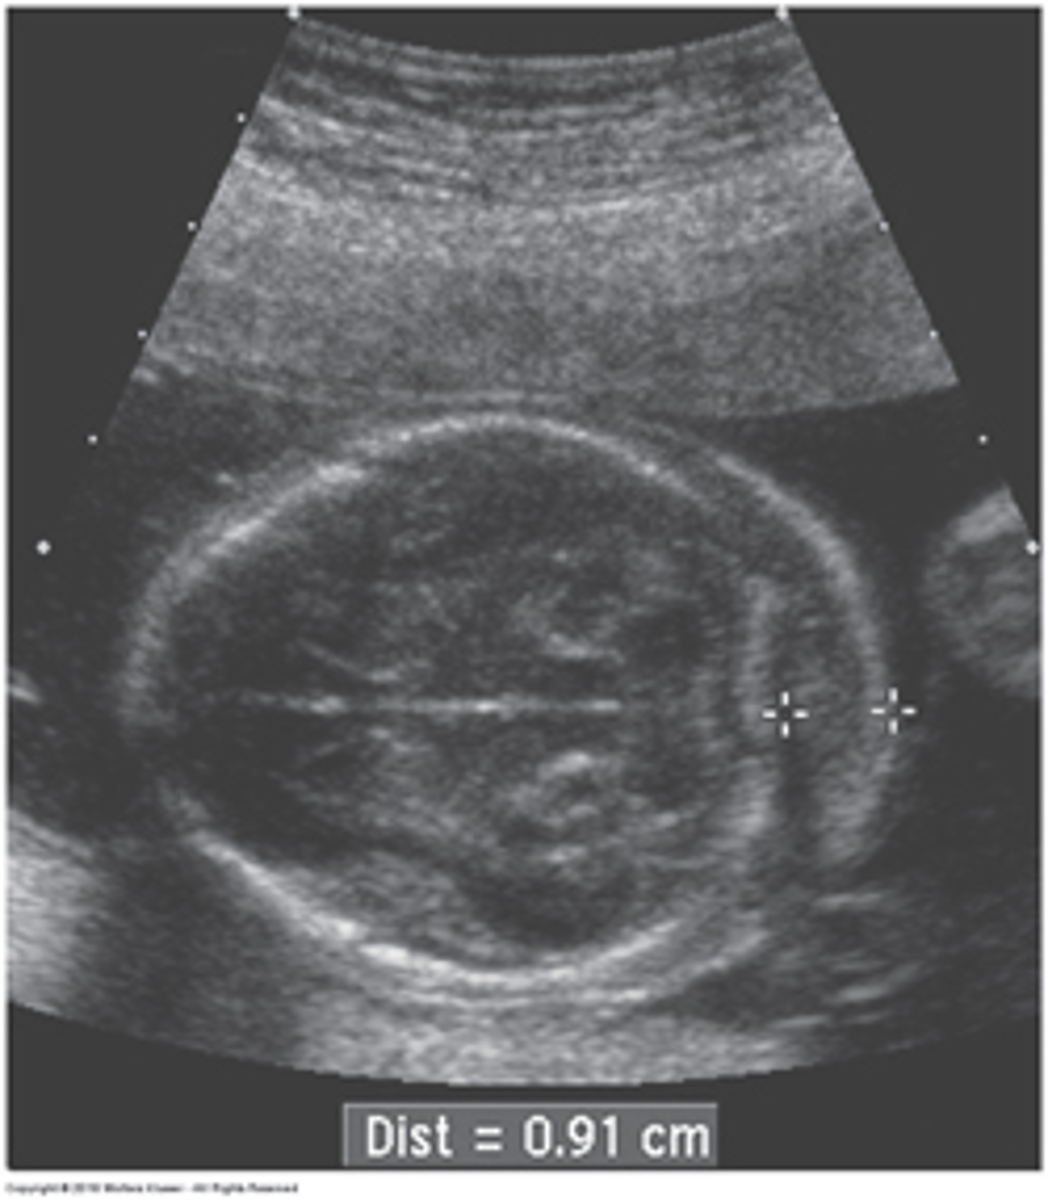

Grade 0 Hydronephrosis

Normal kidney

Grade 1 Hydronephrosis - Pyelectasis

Fluid within renal pelvis, but small enough to be considered insignificant/within normal range